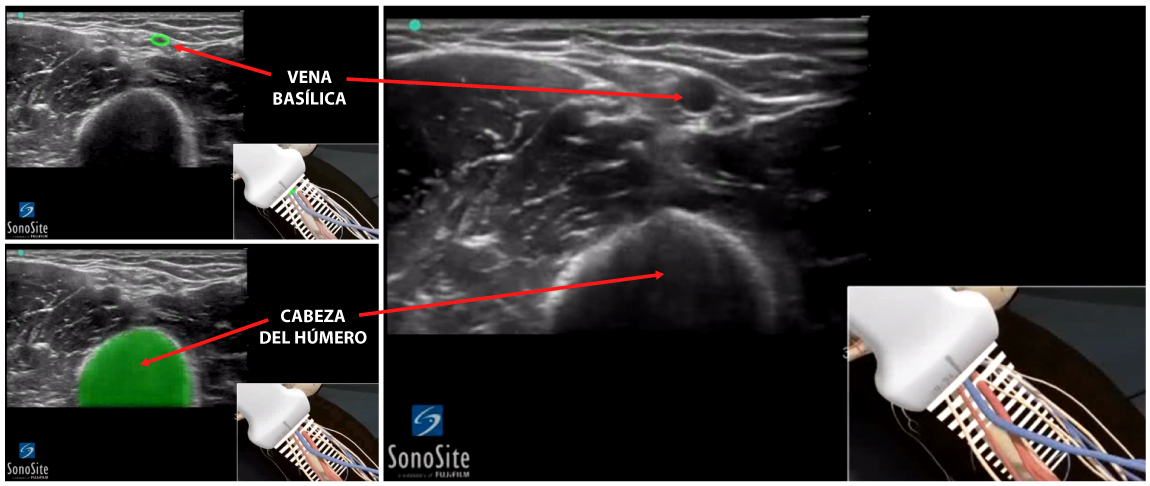

- En el eje transversal la vena basílica se visualiza como una estructura circular anecoica oscura en la parte media de la imagen ecográfica entre los músculos bíceps y tríceps. Más profundamente y un poco a la derecha de la pantalla puede verse el húmero, hiperecoico y brillante. Por consenso, la parte superior de la imagen se considera la superficie de la piel.

Relación Vena Basílica / Vasos Braquiales: